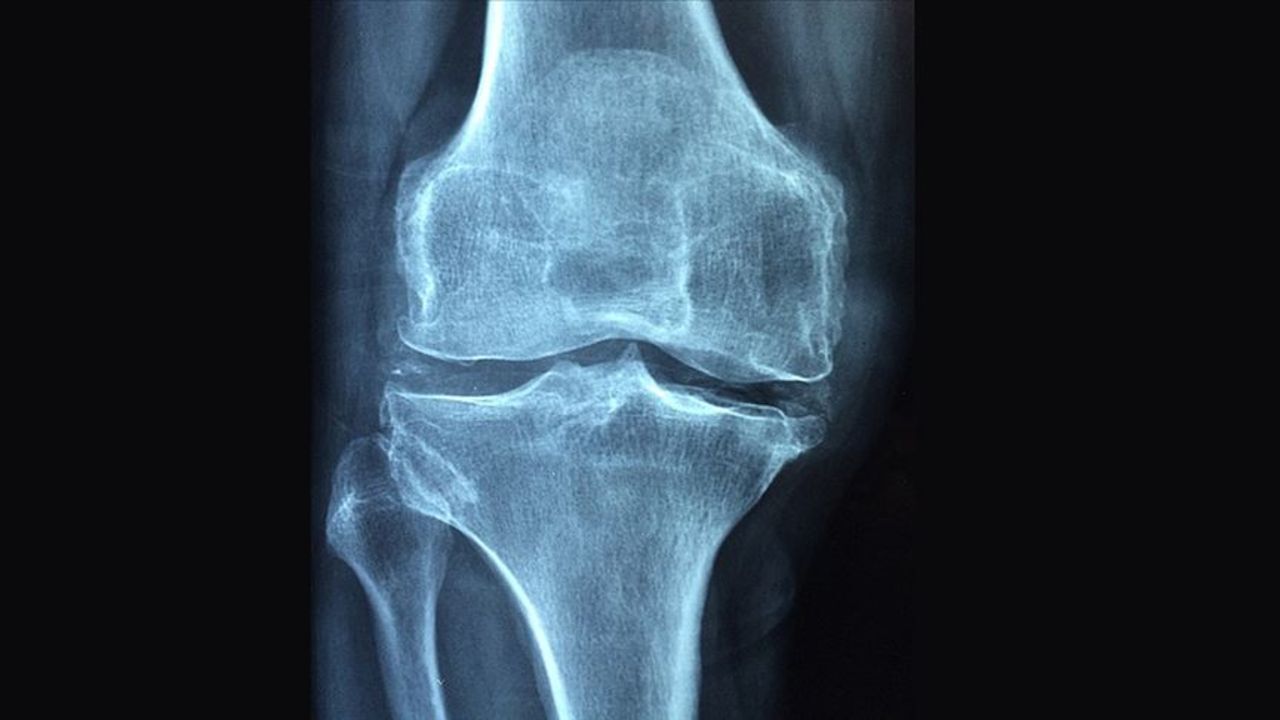

Tıp dünyasında çığır açan buluş: Kemik kırıklarını 3 dakikada onaran yapıştırıcı!

Çinli bilim insanları, kırıkları dakikalar içinde iyileştiren ‘kemik yapıştırıcısı’ geliştirdi. Tek enjeksiyonla uygulanan kemik yapıştırıcı Bone-02, metal plaka ve vidalara gerek kalmadan sadece 3 dakikada kemikleri sabitliyor. İlk testlerde enfeksiyon riskini azalttığı ve ikinci ameliyata ihtiyaç bırakmadığı görüldü.